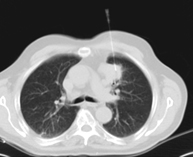

CT-guided thoracic FNA (fine needle aspiration)

This test obtains a sample of tissue from thoracic lesions, such as lung masses, mediastinal masses, bone lesions, etc. This test is performed using local anaesthesia on the puncture area, which is administered with fine-gauge needles. The entire procedure is performed with guidance from images obtained by computed tomography (CT) at various stages of the puncture, using fluoroscopy-CT equipment. After the test, the patient remains in hospital for a few hours. Coagulation tests must be performed before the puncture.